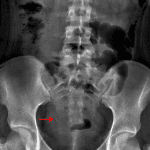

Age: 16

Sex: Female

Indication: Right flank pain

Findings

- Nonobstructive bowel gas pattern

- No abnormal intraabdominal mass effect

- Irregular calcification measuring approximately 4 mm overlying the expected location of the right ureterovesicular junction

Diagnosis

- Ureterovesicular junction (UVJ) stone

Nonobstructive bowel gas pattern.

No abnormal intraabdominal mass effect.

Irregular calcification measuring approximately 4 mm overlying the expected location of the right ureterovesicular junction. This calcification could alternatively be in the bladder or fecal stream. Consider noncontrast CT of the abdomen and pelvis for further evaluation.